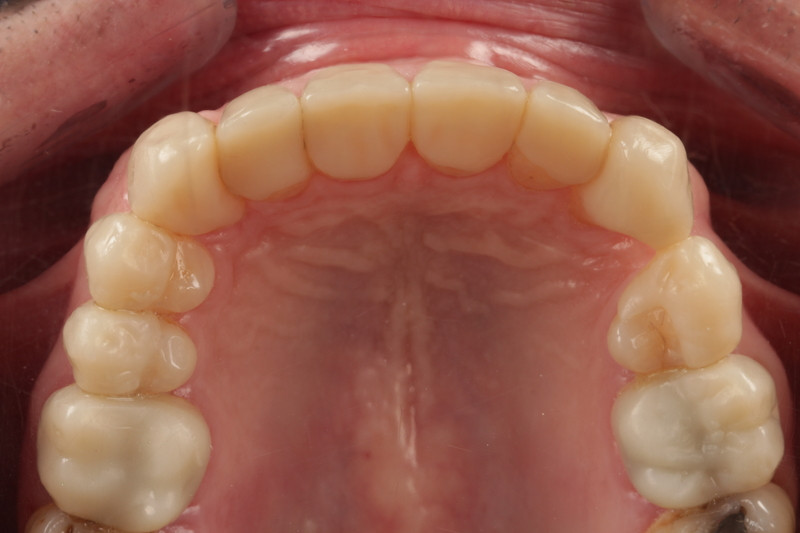

Final outcome

- Patient was extremely happy with the immediate final aesthetic result and reported no issues with adapting to the new OVD and restorations over the subsequent weeks.

- He was reviewed at two weeks, one month, two months and finally three months, and was delighted with no concerns.

Both the team at Avant Garde Laboratories and I are delighted with the result and provide confidence in treating complex cases with 3D Printed materials. The digital design workflow allowed us to be efficient and precise as we were able to share ideas, print models and restorations without delay.

Minimally invasive preparations and biological preservation meant no tooth was prepped into dentine that was already exposed. We managed to preserve significant amounts of enamel for bonding and reducing risk of pulpal flare up.

The case was successful owing to our Patient-centered approach and open communication throughout.